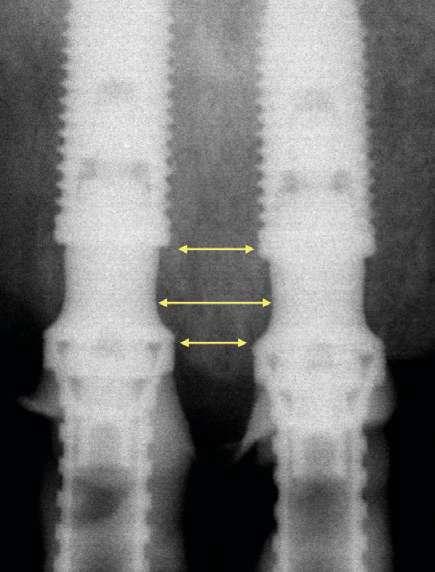

produce una situación similar. El inconveniente que se puede producir en estos casos es la posibilidad de la aparición de una recesión de la mucosa periimplantaria alrededor del pilar precisamente por la combinación de quedar la zona sin soporte óseo y por el propio volumen excesivo que ocupa el pilar. Por el contrario, mediante la utilización de los nuevos perfiles no existe necesidad de remodelar el reborde alveolar y conjuntamente al menor volumen que ocupan los pilares, el tejido (si es suficiente) será capaz de mantenerse en mayor medida. En las figuras 15 a 18 (Fig.15-18) se describe una situación común donde se utiliza el pilar Multi-unit de 17º. En pacientes edéntulos o futuramente edéntulos en la zona de la premaxila. Para maximizar el hueso disponible en esta zona y poder lograr un adecuado torque de inserción es recomendable colocar los implantes en la orientación del hueso, que la gran mayoría de veces discurre en la misma dirección de los bordes incisales de los dientes anteriores. Para compensar y llevar la emergencia de los accesos de los tornillos protésicos hacia palatino se utiliza un pilar Multi-unit de 17º. El dilema en esta zona recae en qué altura de pilar utilizar. Si se utiliza un pilar de 3,5mm de altura, existe el riesgo de reducir el espacio protésico y de nuevo que aparezca una recesión gingival si el implante se coloca a nivel crestal o ligeramente subcrestal (1-1,5mm). Independientemente de la altura seleccionada (2,5mm o 3,5mm), de nuevo, esta situación implica la remodelación ósea mediante bone mill para acomodar el pilar. En la Fig.10 se observa cómo queda la remodelación circular en el implante en posición #1.2 versus la no remodelación de un pilar de nuevo perfil de altura 3,5mm en un implante colocado 2mm subcrestal. La limitación de los pilares de 17º clásicos es que emergen muy rápidamente hacia el diámetro de 4,8mm de la plataforma restauradora y de nuevo no existe espacio suficiente para el establecimiento biológico de la altura de tejido supracrestal. Claramente se observa en las radiografías periapicales comparativas a los 3 meses de la colocación como el implante en posición #1.2 tiene signos de remodelación fisiológica. Hecho que no ocurre en los pilares con nuevos perfiles al ofrecer transiciones más suaves que respetan los principios biológicos.